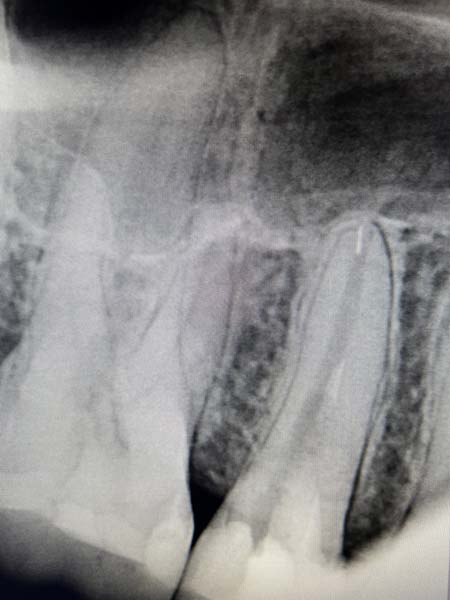

Менеджмент сепарованих ендодонтичних інструментів

"Менеджмент сепарованих ендодонтичних інструментів"

Як не ламати інструменти в кореневих каналах: причини та фактори ризику?

Сепаровані файли і прогноз ендодонтичного лікування: доказова база

Детальний розбір методів вилучення сепарованих ендодонтичних інструментів з кореневого каналу (з мікроскопом і без)

Коли ризик перевищує користь: в яких випадках вилучені інструменти ліпше не вилучати із кореневого каналу? Що робити з ускладненнями при вилученні сепарованих ендодонтичних інструментів?